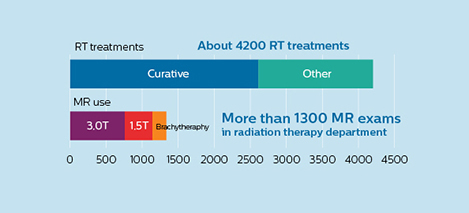

At UMC Utrecht, Dr. Philippens and her colleagues are using MRI in planning external beam radiation therapy (EBRT) for treatment of tumors in a variety of anatomies, such as organs in the pelvis (including bladder, prostate, rectum and cervix), the brain, the esophagus, pancreas, the larynx and oropharynx, bone metastases and sarcomas. In addition, MRI is also used to guide brachytherapy in the prostate and cervix. [6]

The University Medical Center Utrecht Department of Radiotherapy is a leading center in radiation therapy, continuously striving to improve methods and provide excellent patient care. UMC Utrecht has two Philips Ingenia MR-RT systems (1.5T and 3.0T) for RT treatment simulation as well as a Philips Ingenia 1.5T system dedicated for brachytherapy. Furthermore, it is an Atlantic MR-Linac consortium member.